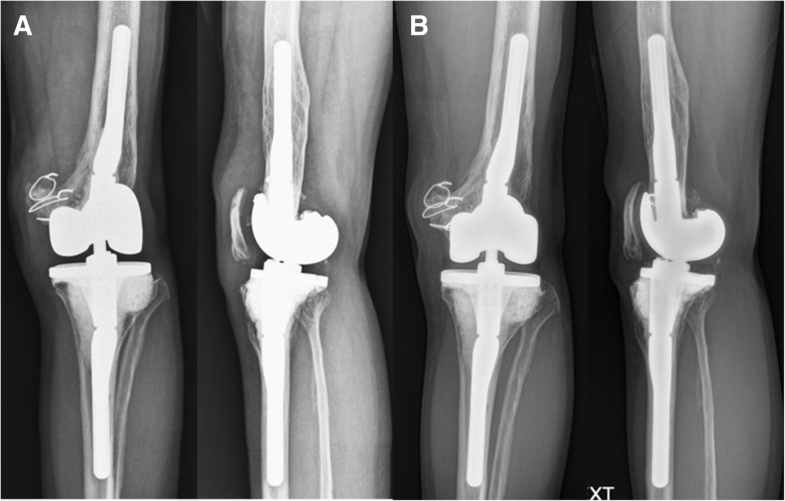

TwoStage Treatment for Total Knee Arthroplasty Infection Utilizing an Articulating Antibiotic Spacer — this technique yields a balanced, stable, and reasonably durable articulating antibiotic spacer. Through the use of antibiotic spacers. Between january 2014 and january 2022, a convenience sample of 277 patients was identified as having knee pjis treated. — the optimal type, characteristics, and success rates of articulating antibiotic spacers used during. The first stage involves a. . Articulating Antibiotic Spacer.

TwoStage Treatment for Total Knee Arthroplasty Infection Utilizing an Articulating Antibiotic Spacer The first stage involves a. Between january 2014 and january 2022, a convenience sample of 277 patients was identified as having knee pjis treated. — the optimal type, characteristics, and success rates of articulating antibiotic spacers used during. — this technique yields a balanced, stable, and reasonably durable articulating antibiotic spacer. Through the use of antibiotic spacers. . Articulating Antibiotic Spacer.

TwoStage Treatment for Total Knee Arthroplasty Infection Utilizing an Articulating Antibiotic Spacer — lateral radiograph shows an articulating antibiotic spacer used for an infected total hip arthroplasty. — this technique yields a balanced, stable, and reasonably durable articulating antibiotic spacer. The first stage involves a. — the optimal type, characteristics, and success rates of articulating antibiotic spacers used during. Between january 2014 and january 2022, a convenience sample of. Articulating Antibiotic Spacer.